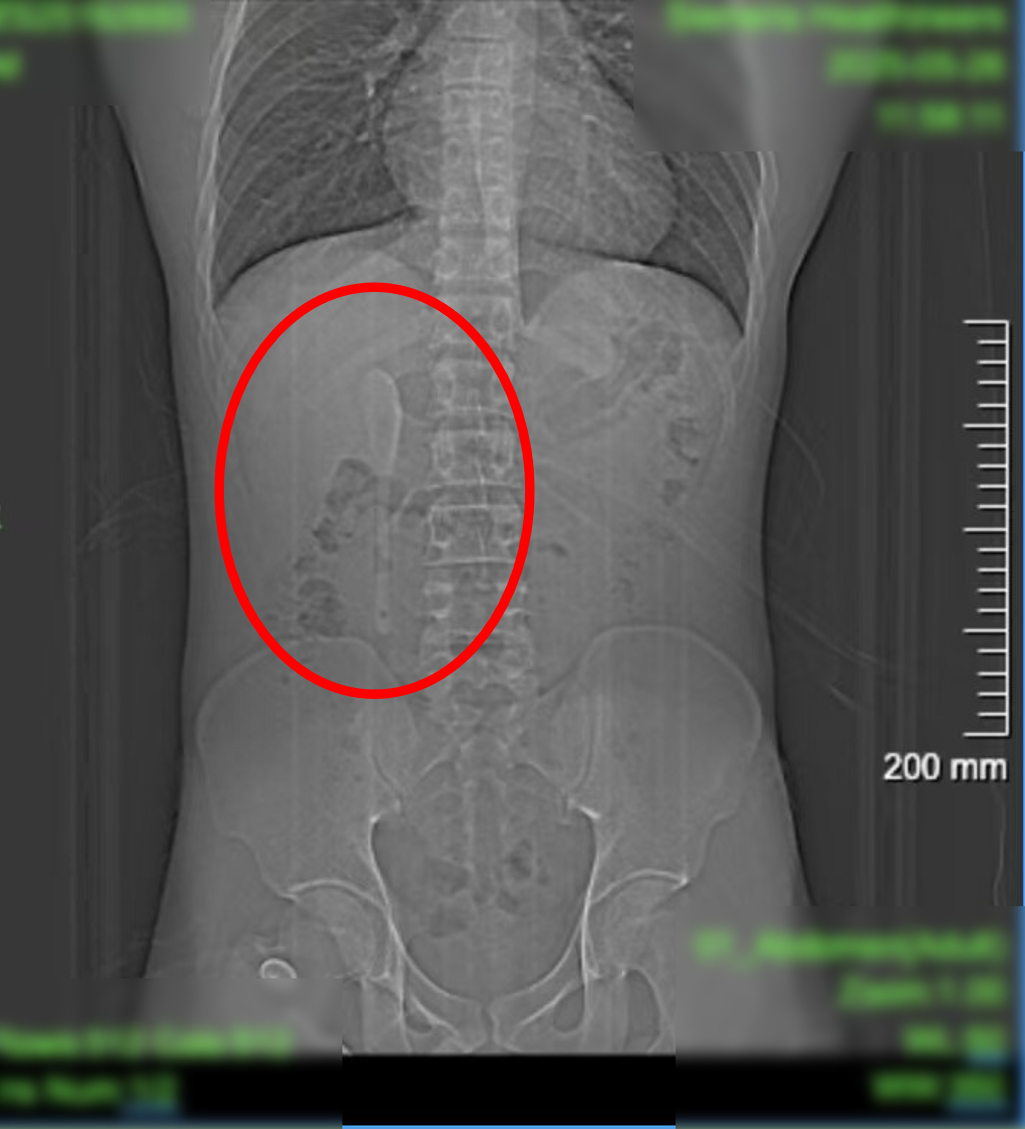

CT显示,这支近15厘米长勺状物体,严丝合缝地横亘于十二指肠球部与降部交界的生理狭窄处,稍有不慎即可能刺穿肠壁,引发腹膜炎或大出血。

中山医院内镜中心主任周平红教授表示,此处腔隙狭窄且肠壁极为菲薄,异物极易嵌顿,稍有不慎容易造成穿孔。

“勺子陶瓷质地光滑细长,十二指肠球降交界又是人体上消化道的生理狭窄处,内镜下取出难度极大。若失败,只能开腹手术。”